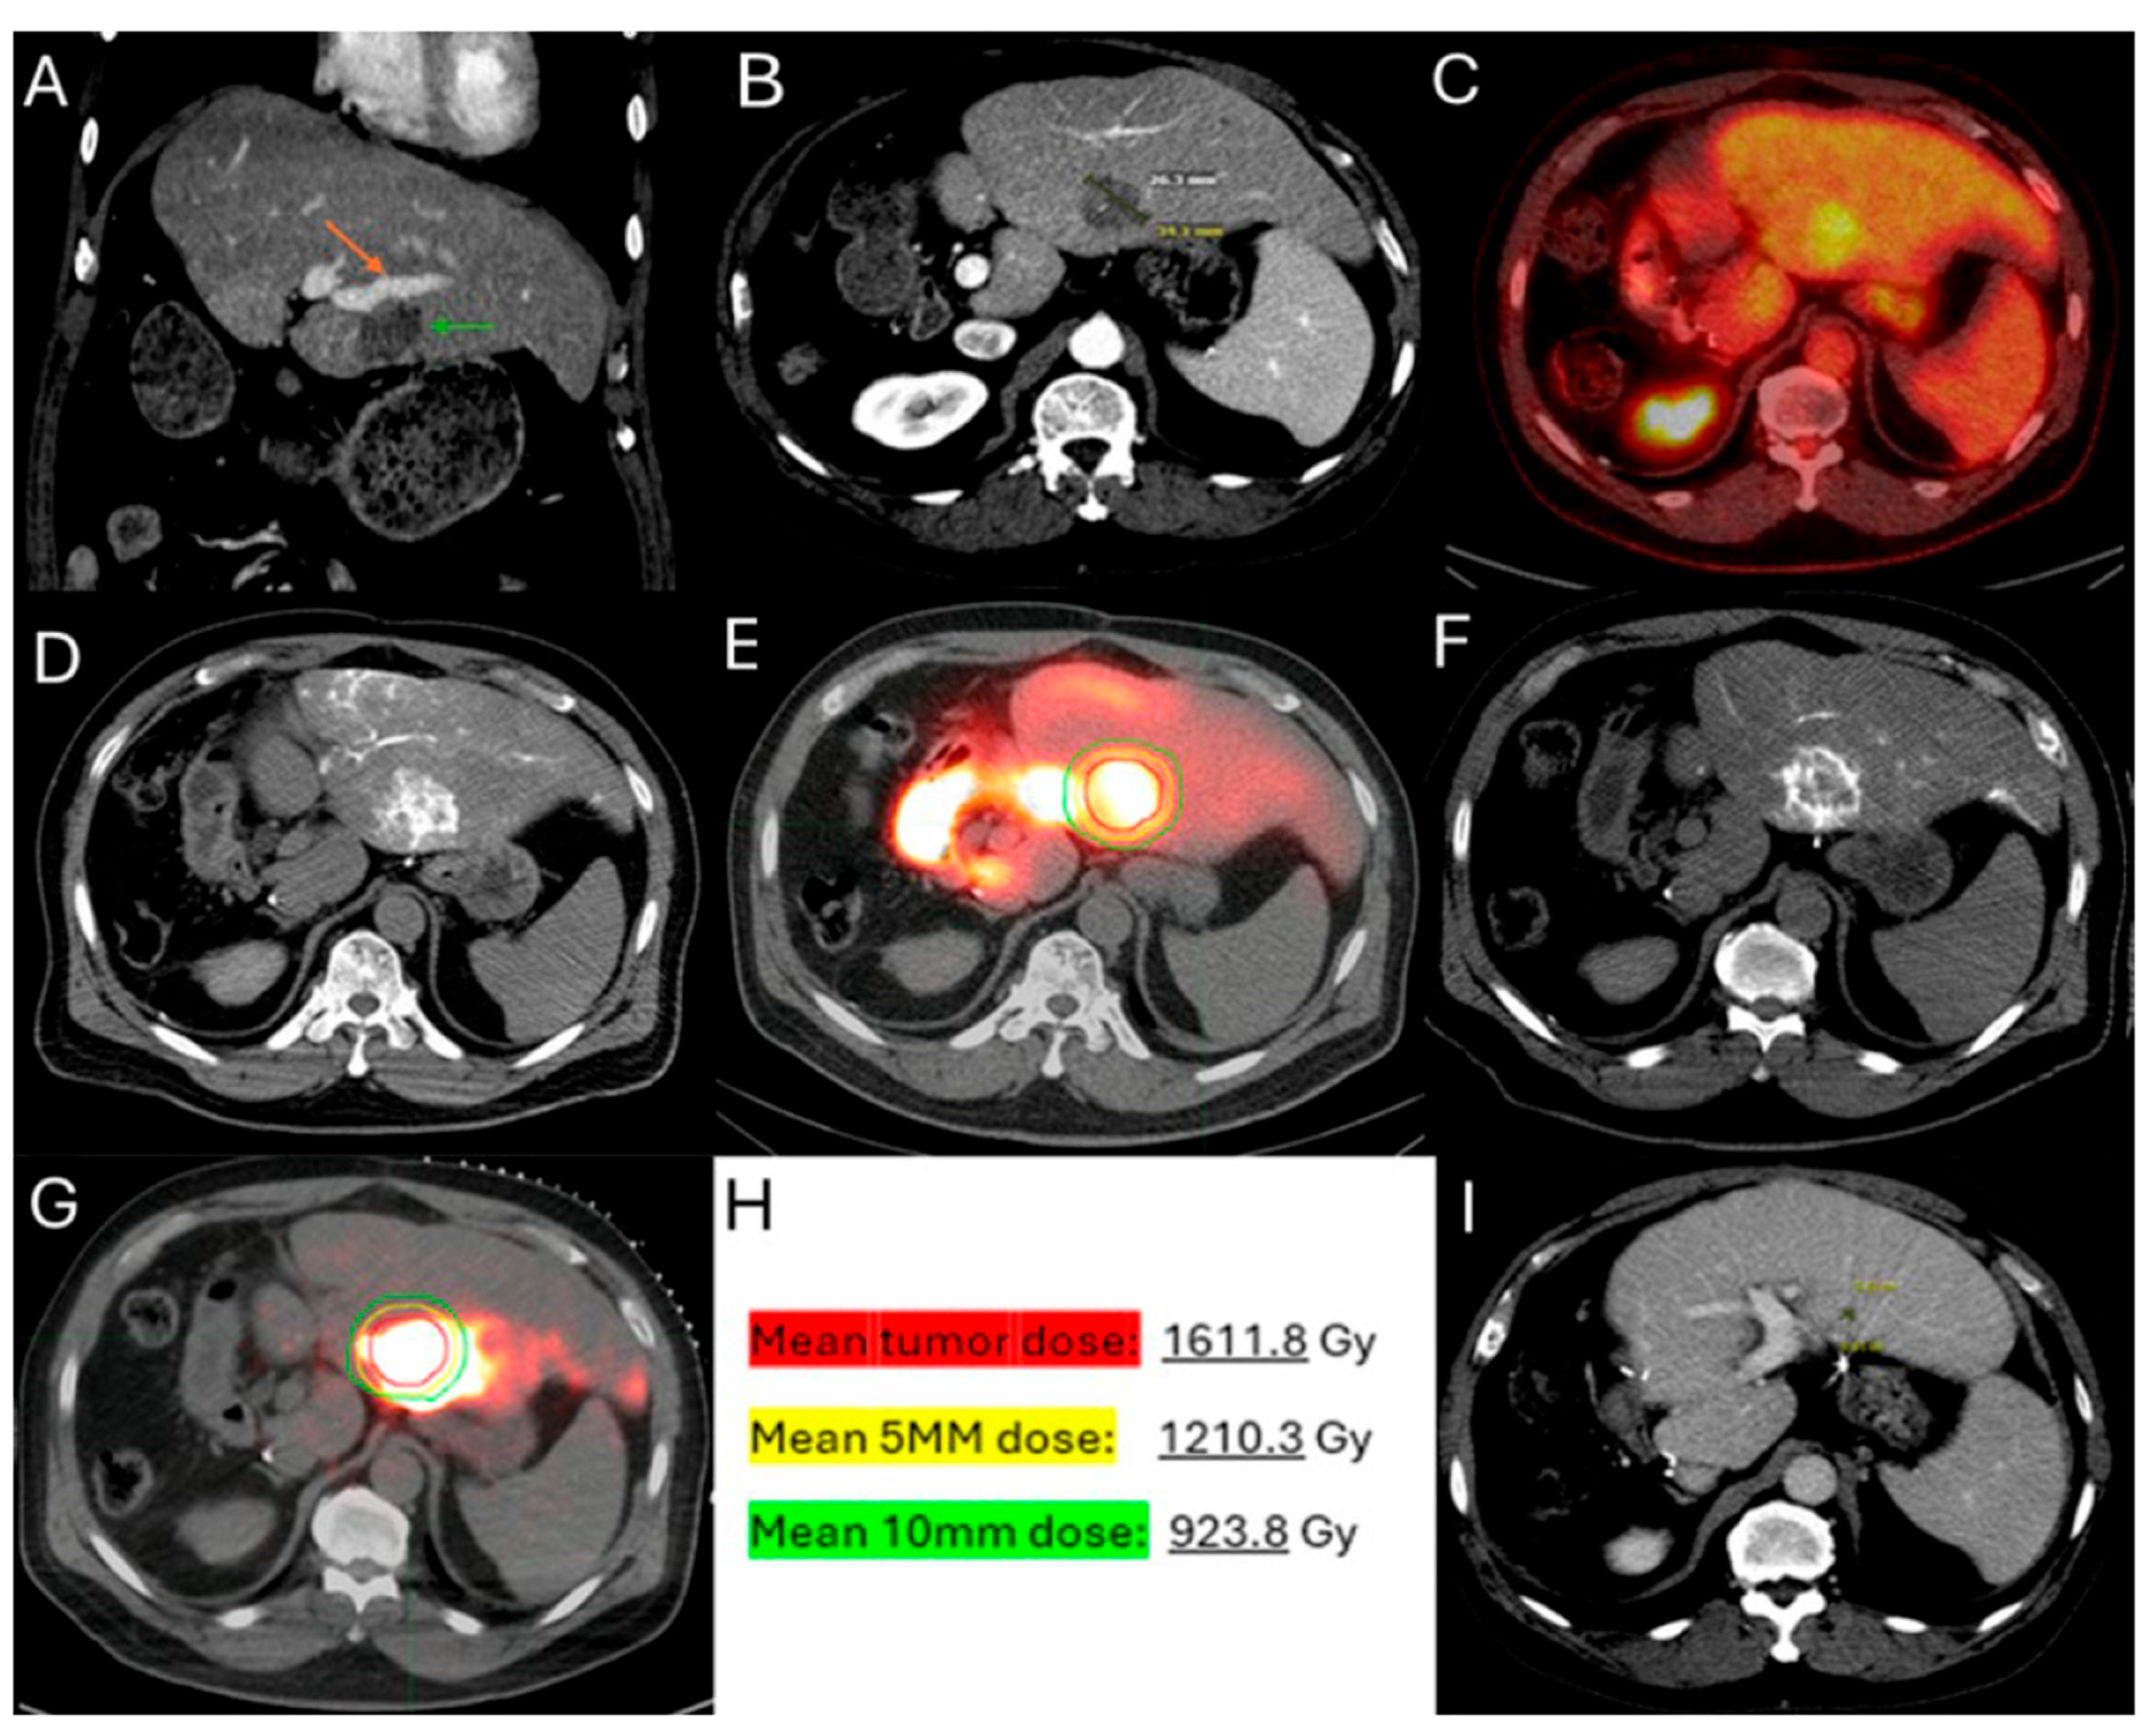

Figure 5.

60-year-old male with history of Neuroblastoma Rat Sarcoma (N-RAS) mutant rectal adenocarcinoma with bilobar liver metastases and prior systemic chemotherapy, right hepatectomy, and left metastasectomies, presents with new metastasis in close proximity to the left portal vein deemed high risk for thermal ablation (A–C). After multidisciplinary review, radiation segmentectomy was recommended as the appropriate therapy to minimize the risk for injury of the nearby portal vein ((A) orange arrowhead indicates the left branch of portal vein, green arrowhead indicates the target tumor). During mapping, CT arteriography demonstrates optimal tumor coverage (D) confirmed by Technetium-99m Macroaggregated Albumin (Tc-99m-MMA SPECT/CT) (E). CT arteriography during TARE (F) and post-TARE bremsstrahlung scan (G) demonstrates optimal target tumor coverage (E,G): the red circle represents the tumor contours, while the yellow the 5 mm and the green the 10 mm margin areas around the target tumor. The mean tumor absorbed dose is 1611.8 Gray (Gy), the mean 5 mm absorbed dose 1210.3 Gy, and the mean 10 mm margin absorbed dose is 923.8 Gy according to dosimetry workflow of MIM DEV version 3.3.7. (H). Follow-up ceCT at 2 years indicates sustained long-term tumor control (I).